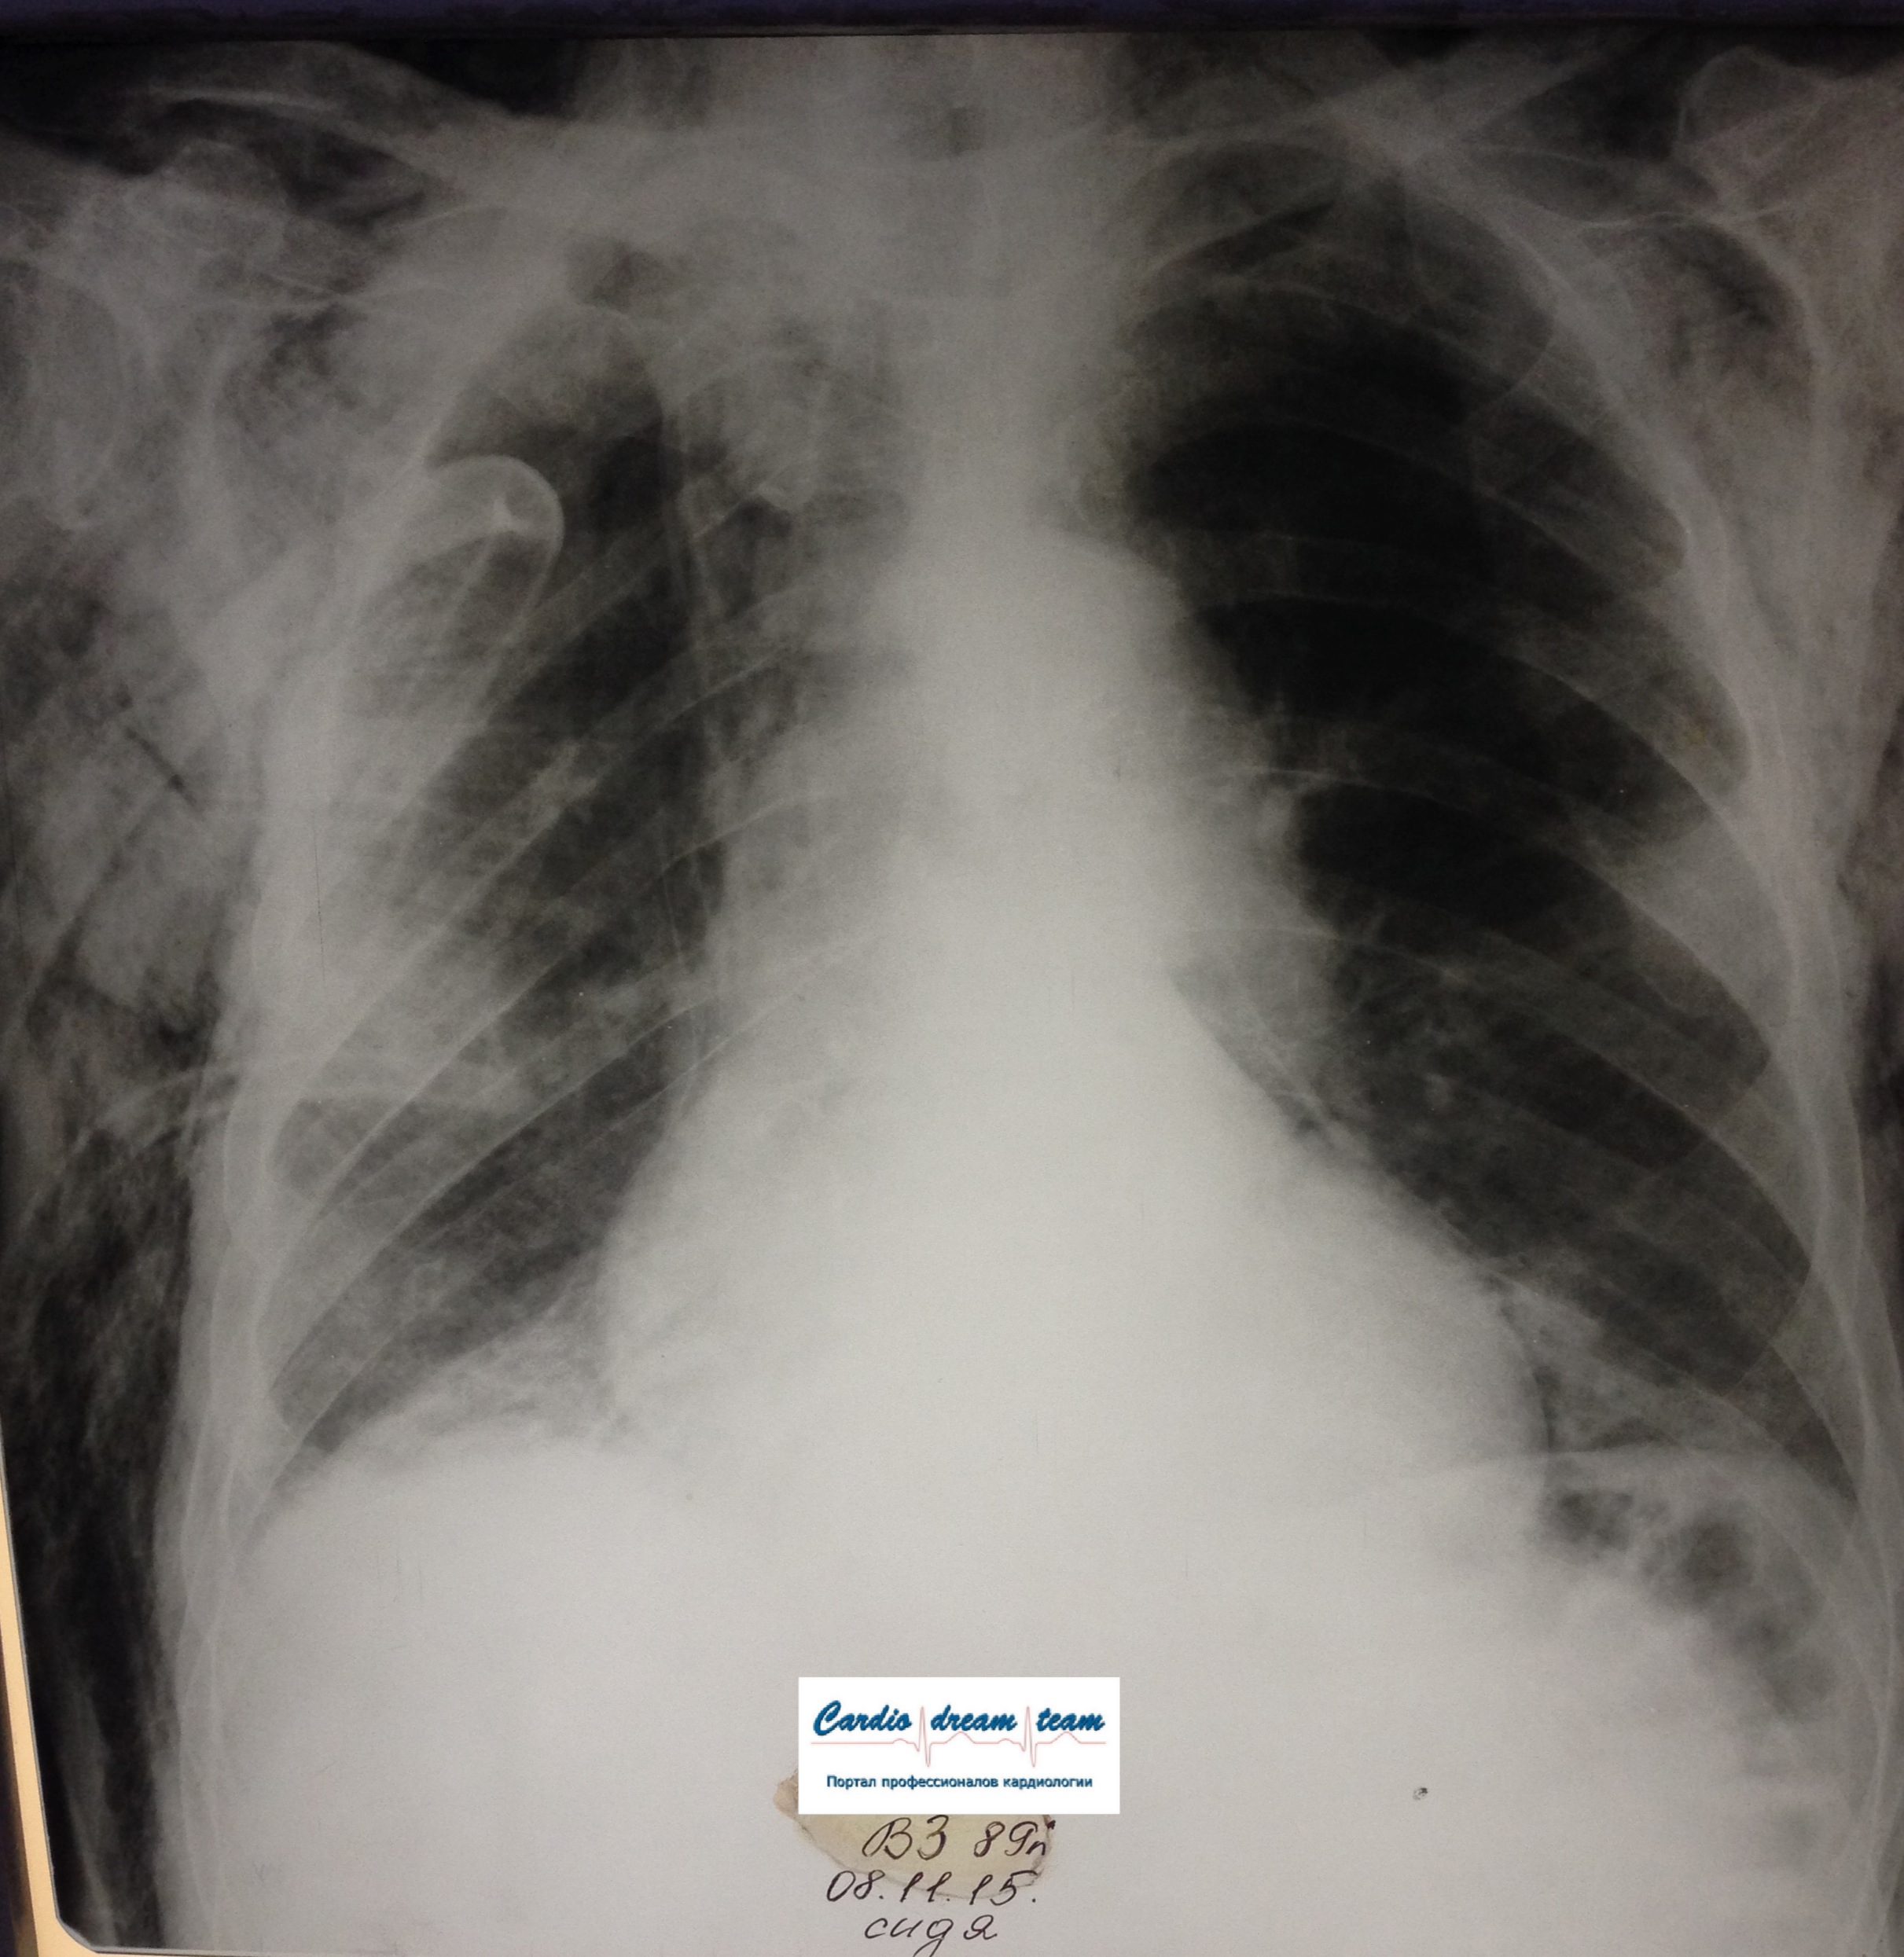

ИССЛЕДОВАНИЕ ОРГАНОВ ГРУДНОЙ КЛЕТКИ Дата 01-ОКТ-15 время 11.30 ОПИСАНИЕ: Проведена рентгенография органов грудной клетки в прямой проекции, положение сидя, условия ПИТ, Р-контроль Легочные поля: Справа легкое расправлено не полностью, апикально до 3го ребра прослеживается свободный газ в плевральной полости. Тень дренажа справа. Тень подключичного катетера в проекции ВПВ. Легочный рисунок: сгущен справа в прикорневой зоне, диффузно деформирован Корни: малоструктурны, обогащены Синусы: нечеткие Сердце: широко лежит на диафрагме (позиционно) ЗАКЛЮЧЕНИЕ: Течение правостороннего пневмоторакса, положительная Р-динамика. Состояние дренирования правой плевральной полости. Р-признаки полнокровия сосудов МКК. Пневмосклероз. Р-контроль .────────────────────────────────────────────────────────────────────── ИССЛЕДОВАНИЕ ОРГАНОВ ГРУДНОЙ КЛЕТКИ Дата 02-ОКТ-15 время 1015 ОПИСАНИЕ: